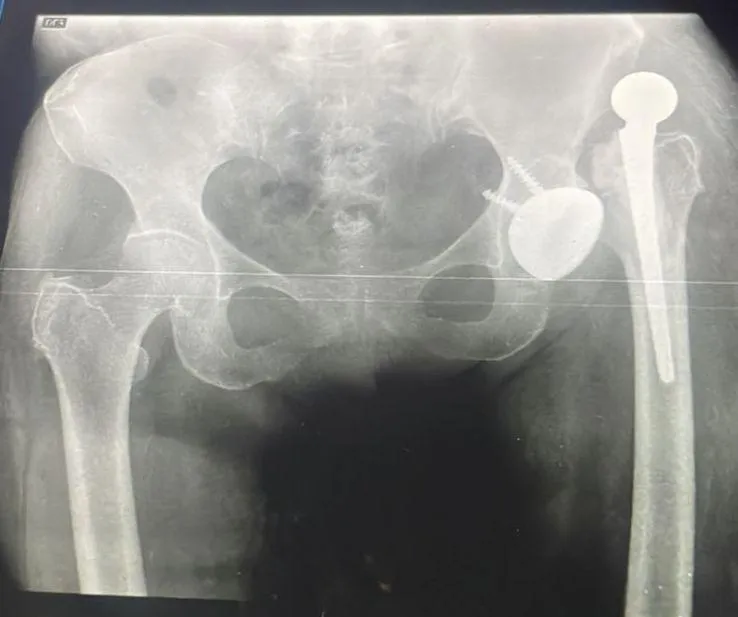

Fractura Antigua

Fractura antigua de cadera tratada con prótesis de doble movilidad

Fractura de cadera de larga evolución. Se realizó procedimiento quirúrgico con colocación de prótesis de doble movilidad.